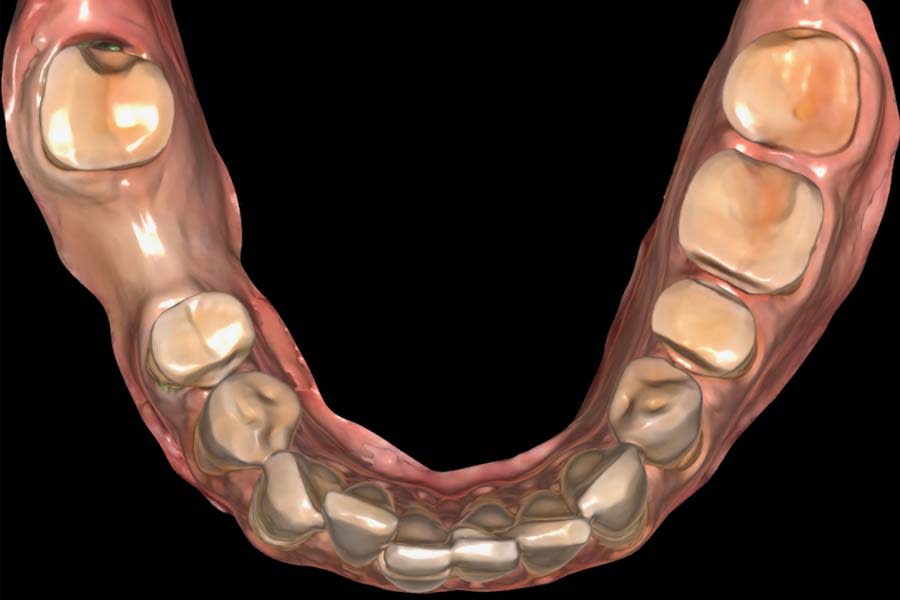

Intraoral and extraoral photographs and digital scans were obtained. Bite registration was taken in centric relation, along with three additional registrations at 1 mm, 1.5 mm, and 2 mm increased OVD using a leaf gauge. Medical and dietary history revealed mild gastric reflux and habitual tea consumption. Clinical examination identified multifactorial wear, with signs of intrinsic and extrinsic erosion, attrition, and abrasion (Figure 3 and Figure 4). There was significant tooth structure loss and partial dentoalveolar compensation. The gingival phenotype was thin, with RT1 recession defects at multiple sites.27

Digital smile design was generated using a biomimetic tooth library in a virtual treatment planning software (Smilecloud 3DNA, Smilecloud, smilecloud.com) and presented to the patient for discussion (Figure 5 and Figure 6). A proposed soft-tissue design that included root coverage procedures and an implant placement option for the replacement of tooth No. 30 was also reviewed. Surgical procedures would be deferred because the patient was planning a relocation within 2 months; however, she expressed interest in pursuing these procedures in the future. Based on the patient’s chief complaint, esthetic goals, and timeline, the treatment plan included replacing the existing FDP and restoring the worn dentition with a combination of CAD/CAM lithium-disilicate partial-coverage indirect restorations and direct composite restorations at a 2 mm increased OVD.

Definitive digital scans of each arch were obtained (Figure 7 and Figure 8), and the definitive restorations were designed based on the diagnostic wax-up (Figure 9). The design files were then exported in standard tessellation language (STL) format and transferred to the in-house technicians for milling of the definitive restorations in lithium-disilicate material. The restorations were subsequently custom-stained and glazed (Figure 10). Based on the patient’s esthetic preferences, modifications were made to the maxillary anterior design before delivery. The definitive restorations were evaluated intraorally and bonded with a luting composite (soft white shade) (Variolink® Esthetic LC, Ivoclar) (Figure 11), with all excess cement carefully removed (Figure 12 and Figure 13). The mandibular incisors were restored with direct composite, and abrasion lesions in the esthetic zone, intended for future root coverage, were provisionally restored with supragingival flowable composite for improved appearance (Figure 14).